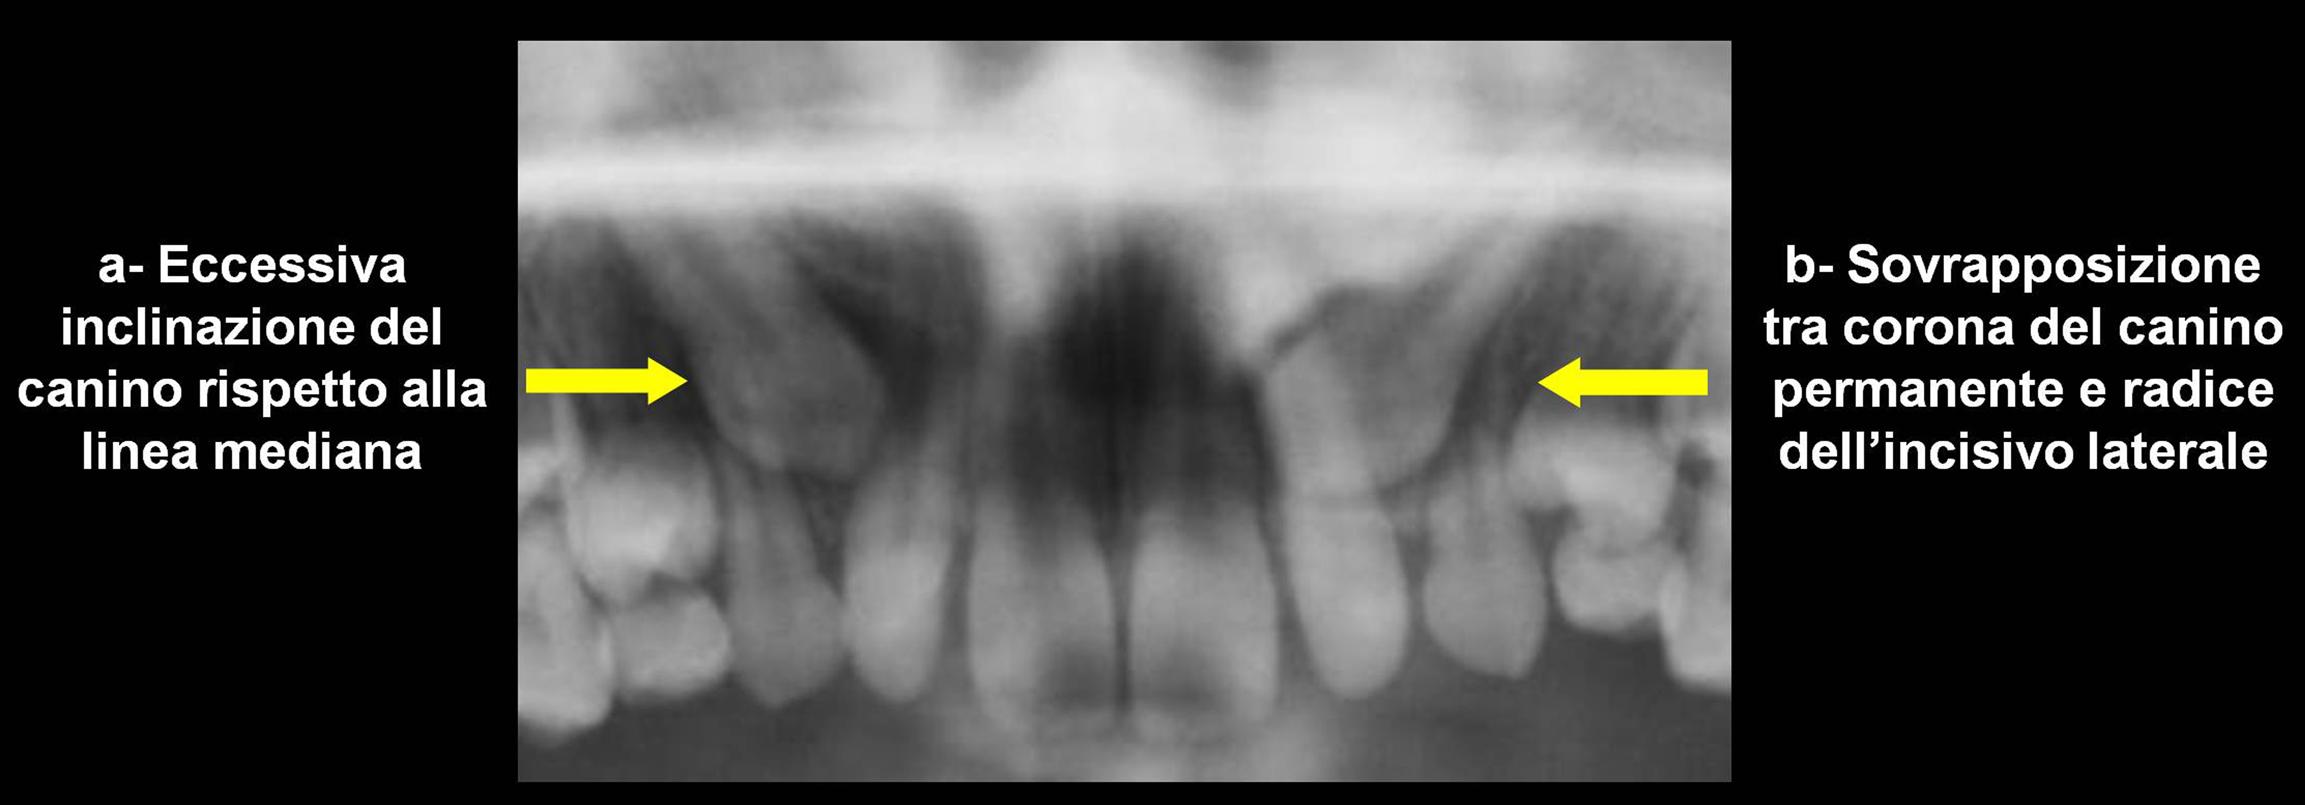

Considerando la posizione del canino su ortopantomografia, la letteratura ortodontica indica i seguenti indicatori di rischio radiografici: 1) l�inclinazione eccessiva (> 25�) dell�asse lungo del canino rispetto alla linea mediana (Figura 4-a); 2) la sovrapposizione tra la corona del canino e la radice dell�incisivo laterale adiacente (Figura 4-b)2.

Figura

4. Indicatori di rischio

radiografici

L�esecuzione di una ortopantomografia � indicata intorno agli 8-9 anni, et� a partire dalla quale si verifica la quota pi� significativa di movimento del canino10. Il rischio di riassorbimento aumenta del 50% quando la cuspide del canino sulla ortopantomografia appare sovrapposta alla radice dell�incisivo laterale e quando l�inclinazione del suo asse � eccessiva (> 25�) rispetto alla linea mediana2.